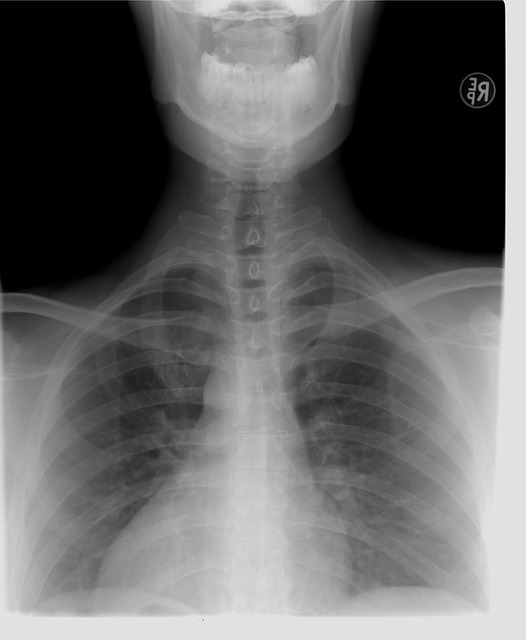

흉통의 진단은 환자의 병력 조사, 신체 검사, 그리고 다양한 진단 검사를 통해 이루어집니다. 심전도, 혈액 검사, 흉부 X선, 심장 초음파 등이 일반적으로 사용됩니다. 이러한 검사를 통해 흉통의 원인을 보다 정확히 파악하고, 적절한 치료 계획을 세울 수 있습니다. 정확한 진단은 효과적인 치료의 핵심입니다.